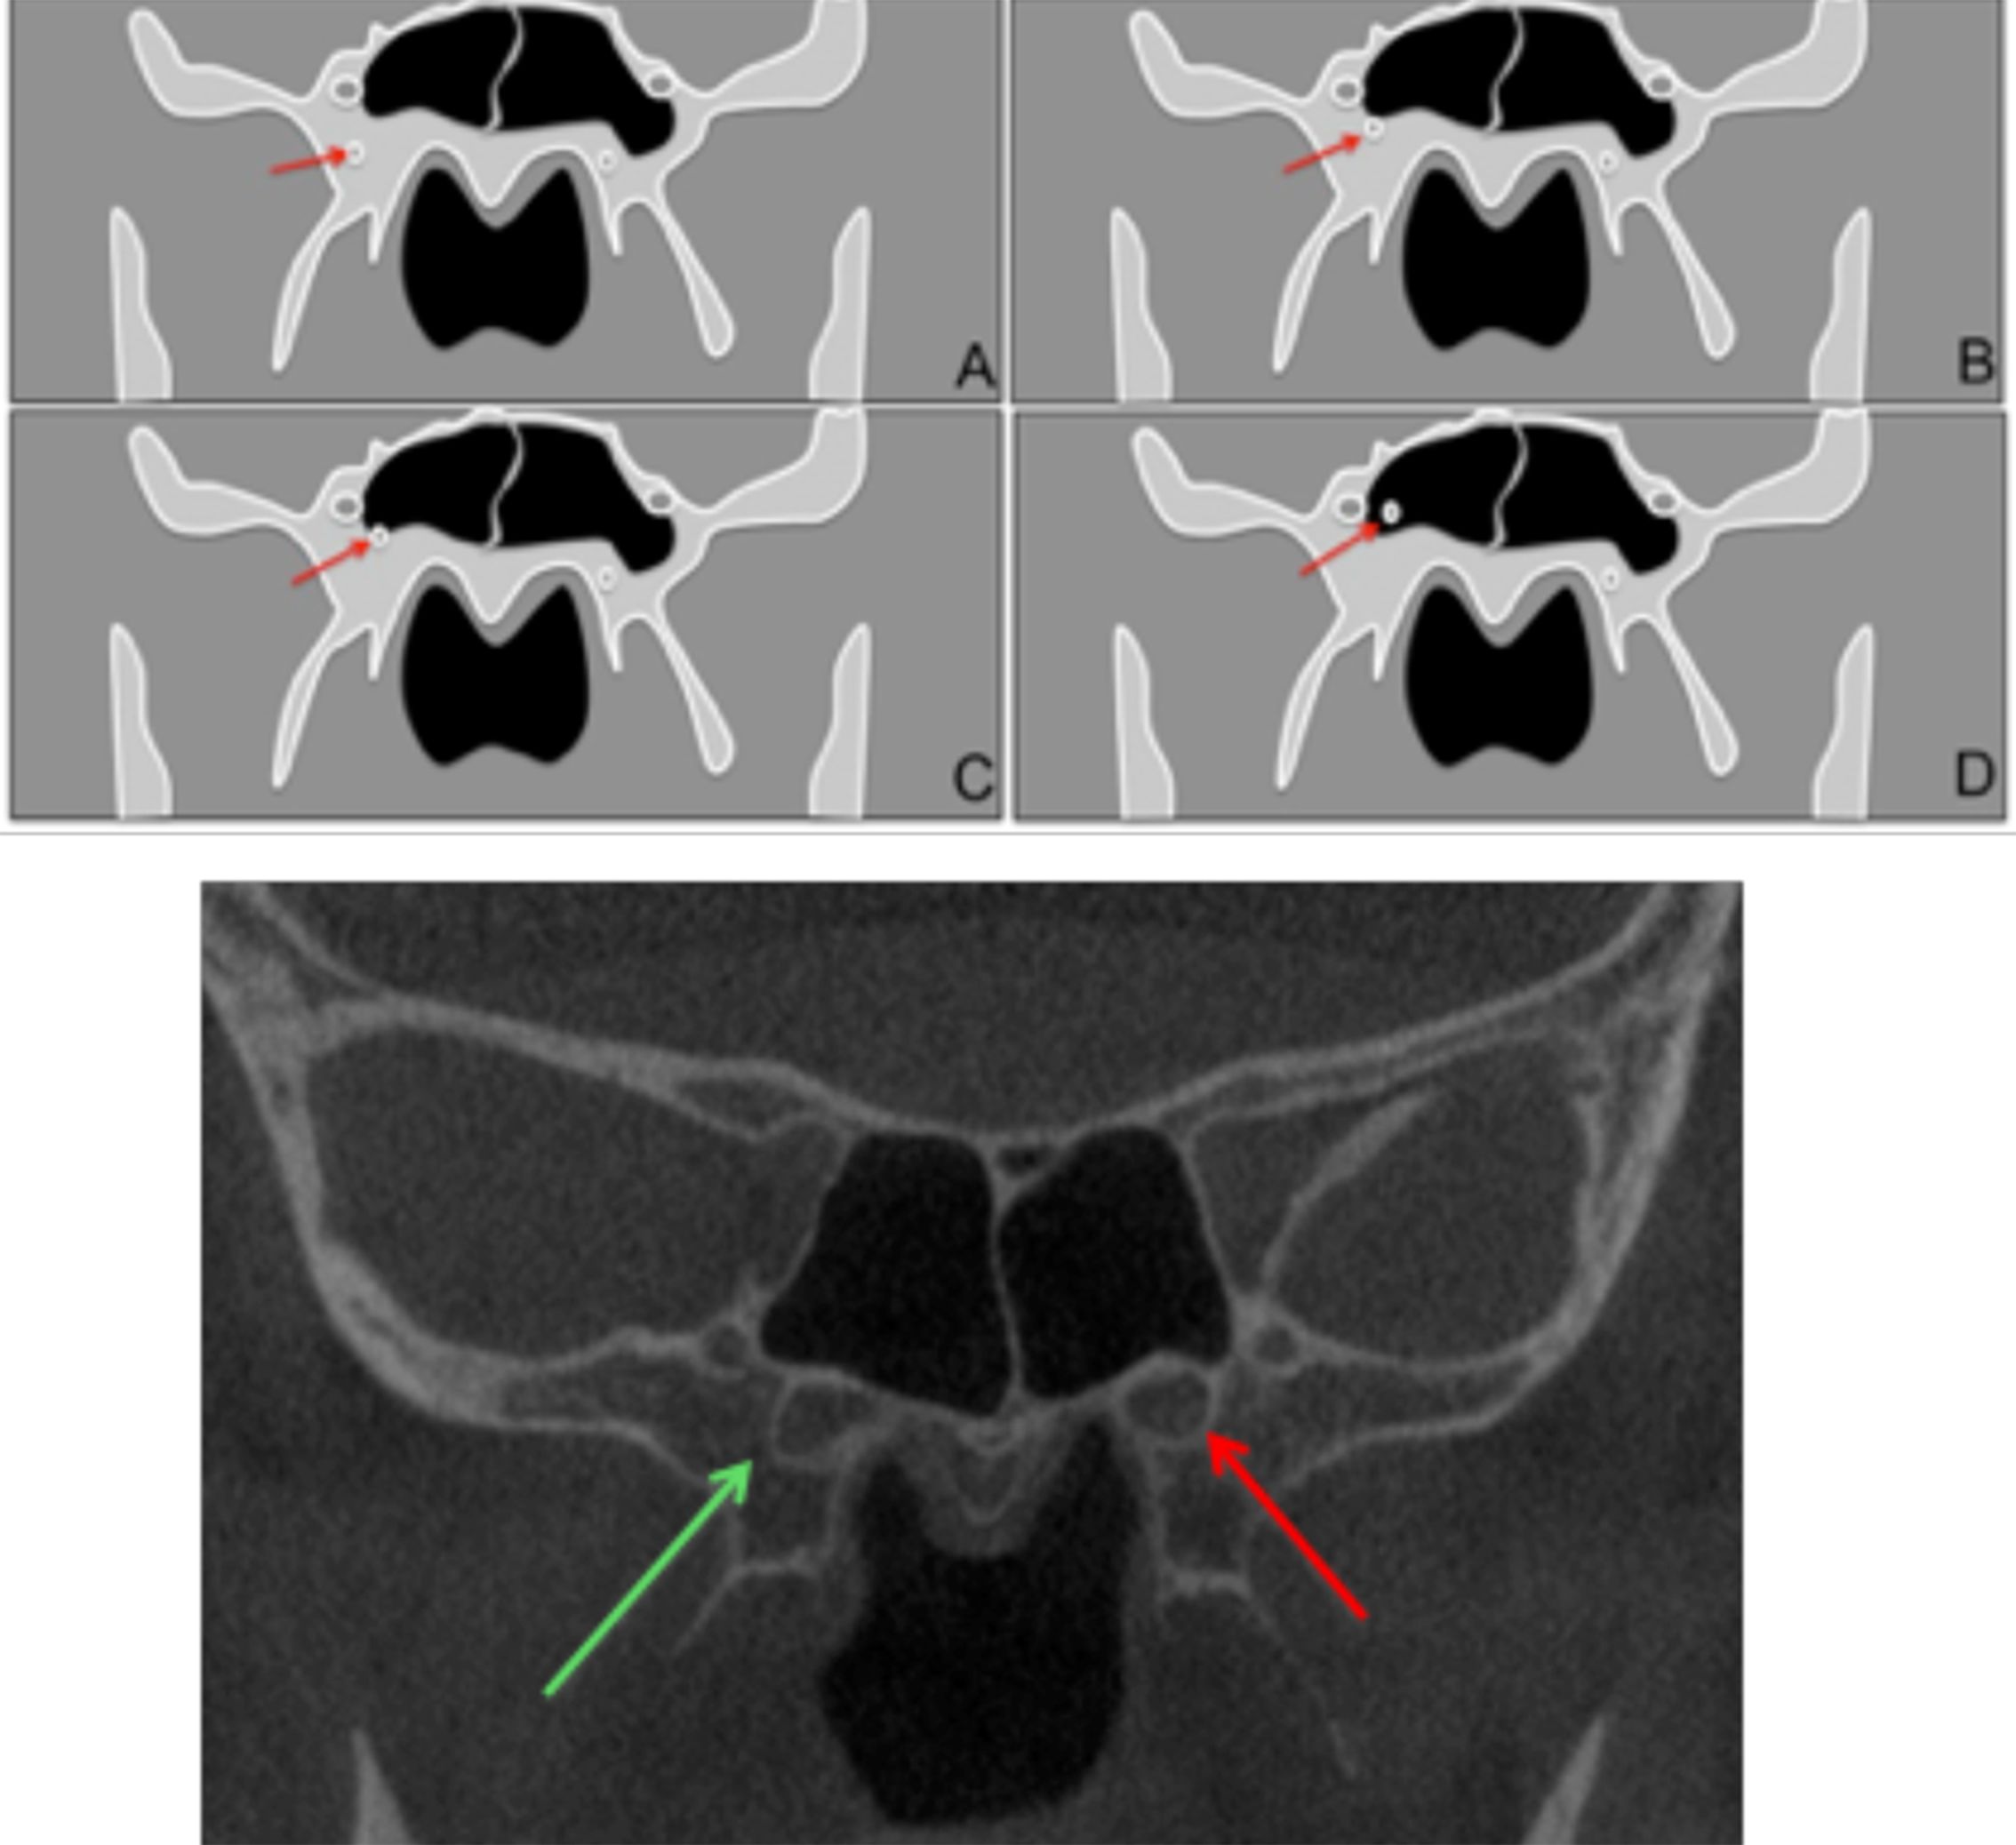

Objective: The aim of this study was to evaluate the pterygoid canal (PC) by Cone Beam Computed Tomography (CBCT), establishing its configuration and proximity with anatomical structures. Material and Methods: We evaluated 398 CBCT exams, all from a public University radiology clinic archive. Four parameters were evaluated: single or double PC, distance between PC and the inferior part of the sphenoid sinus (SS), ratio of PC and SS and the distance between the PC and the foramen rotundum. Results: It was observed that most of the PC of the sample presented simple morphology, the most frequent type of relationship between the PC and the SS on both sides was the close contact with the wall. Among the cases that there were some distances between the PC and the inferior wall of the SS, the mean of this distance did not exceed 3.20 mm, being the left side (3.03 mm) slightly closer than the right (3.20 mm). Finally, the distances between the PC and the corresponding Foramen Rotundum are presented with mean values of 5.87 mm for the right side and 6.31 mm for the left side. Conclusion: CBCT examination is of paramount importance for PC identification; once in the studied sample, the mean values found evidence the close relation between the PC and the SS.